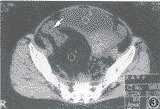

, 百拇医药 CT扫描:盆腔右侧部见多量脂肪密度影,CT值为-77.9 HU,分布以直肠、乙状结肠(右位)周围为主,致肠壁不均匀增厚、肠腔狭窄,并见纤维条索影,显示出“柳条状”结构。膀胱、子宫向左推移(图2,3)。

图3 为图2下一层面,显示肠壁增厚、肠腔狭窄。病变内纤维条索构成典型“柳枝征”